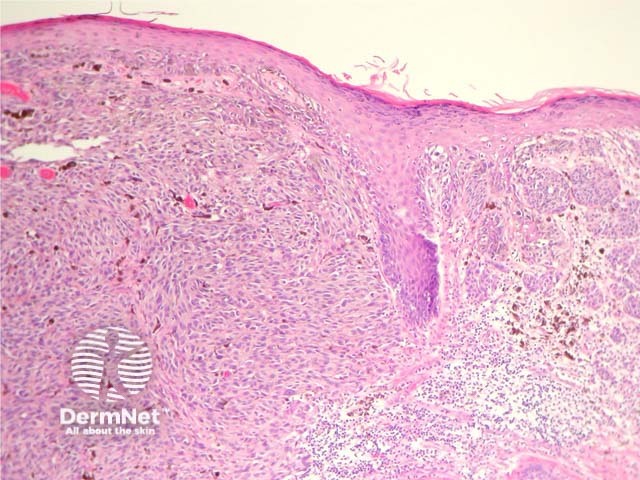

Most melanomas have an initial radial growth phase within the epidermis and sometimes within the papillary dermis (figure 1, 2), which may be followed by a vertical growth phase with deeper extension (figures 3, 4). The exception to this is nodular melanomas, which either skip the radial growth phase or the radial phase is rapidly overrun by the vertically growing tumour. It is also possible that they arise within dermal melanocytes. It has been proposed that lesions in the radial growth phase are incapable of metastasis, however there are numerous examples of thin melanomas that have behaved aggressively, even without convincing evidence of vertical growth.

Figure 1

Figure 2

Figure 3

Figure 4